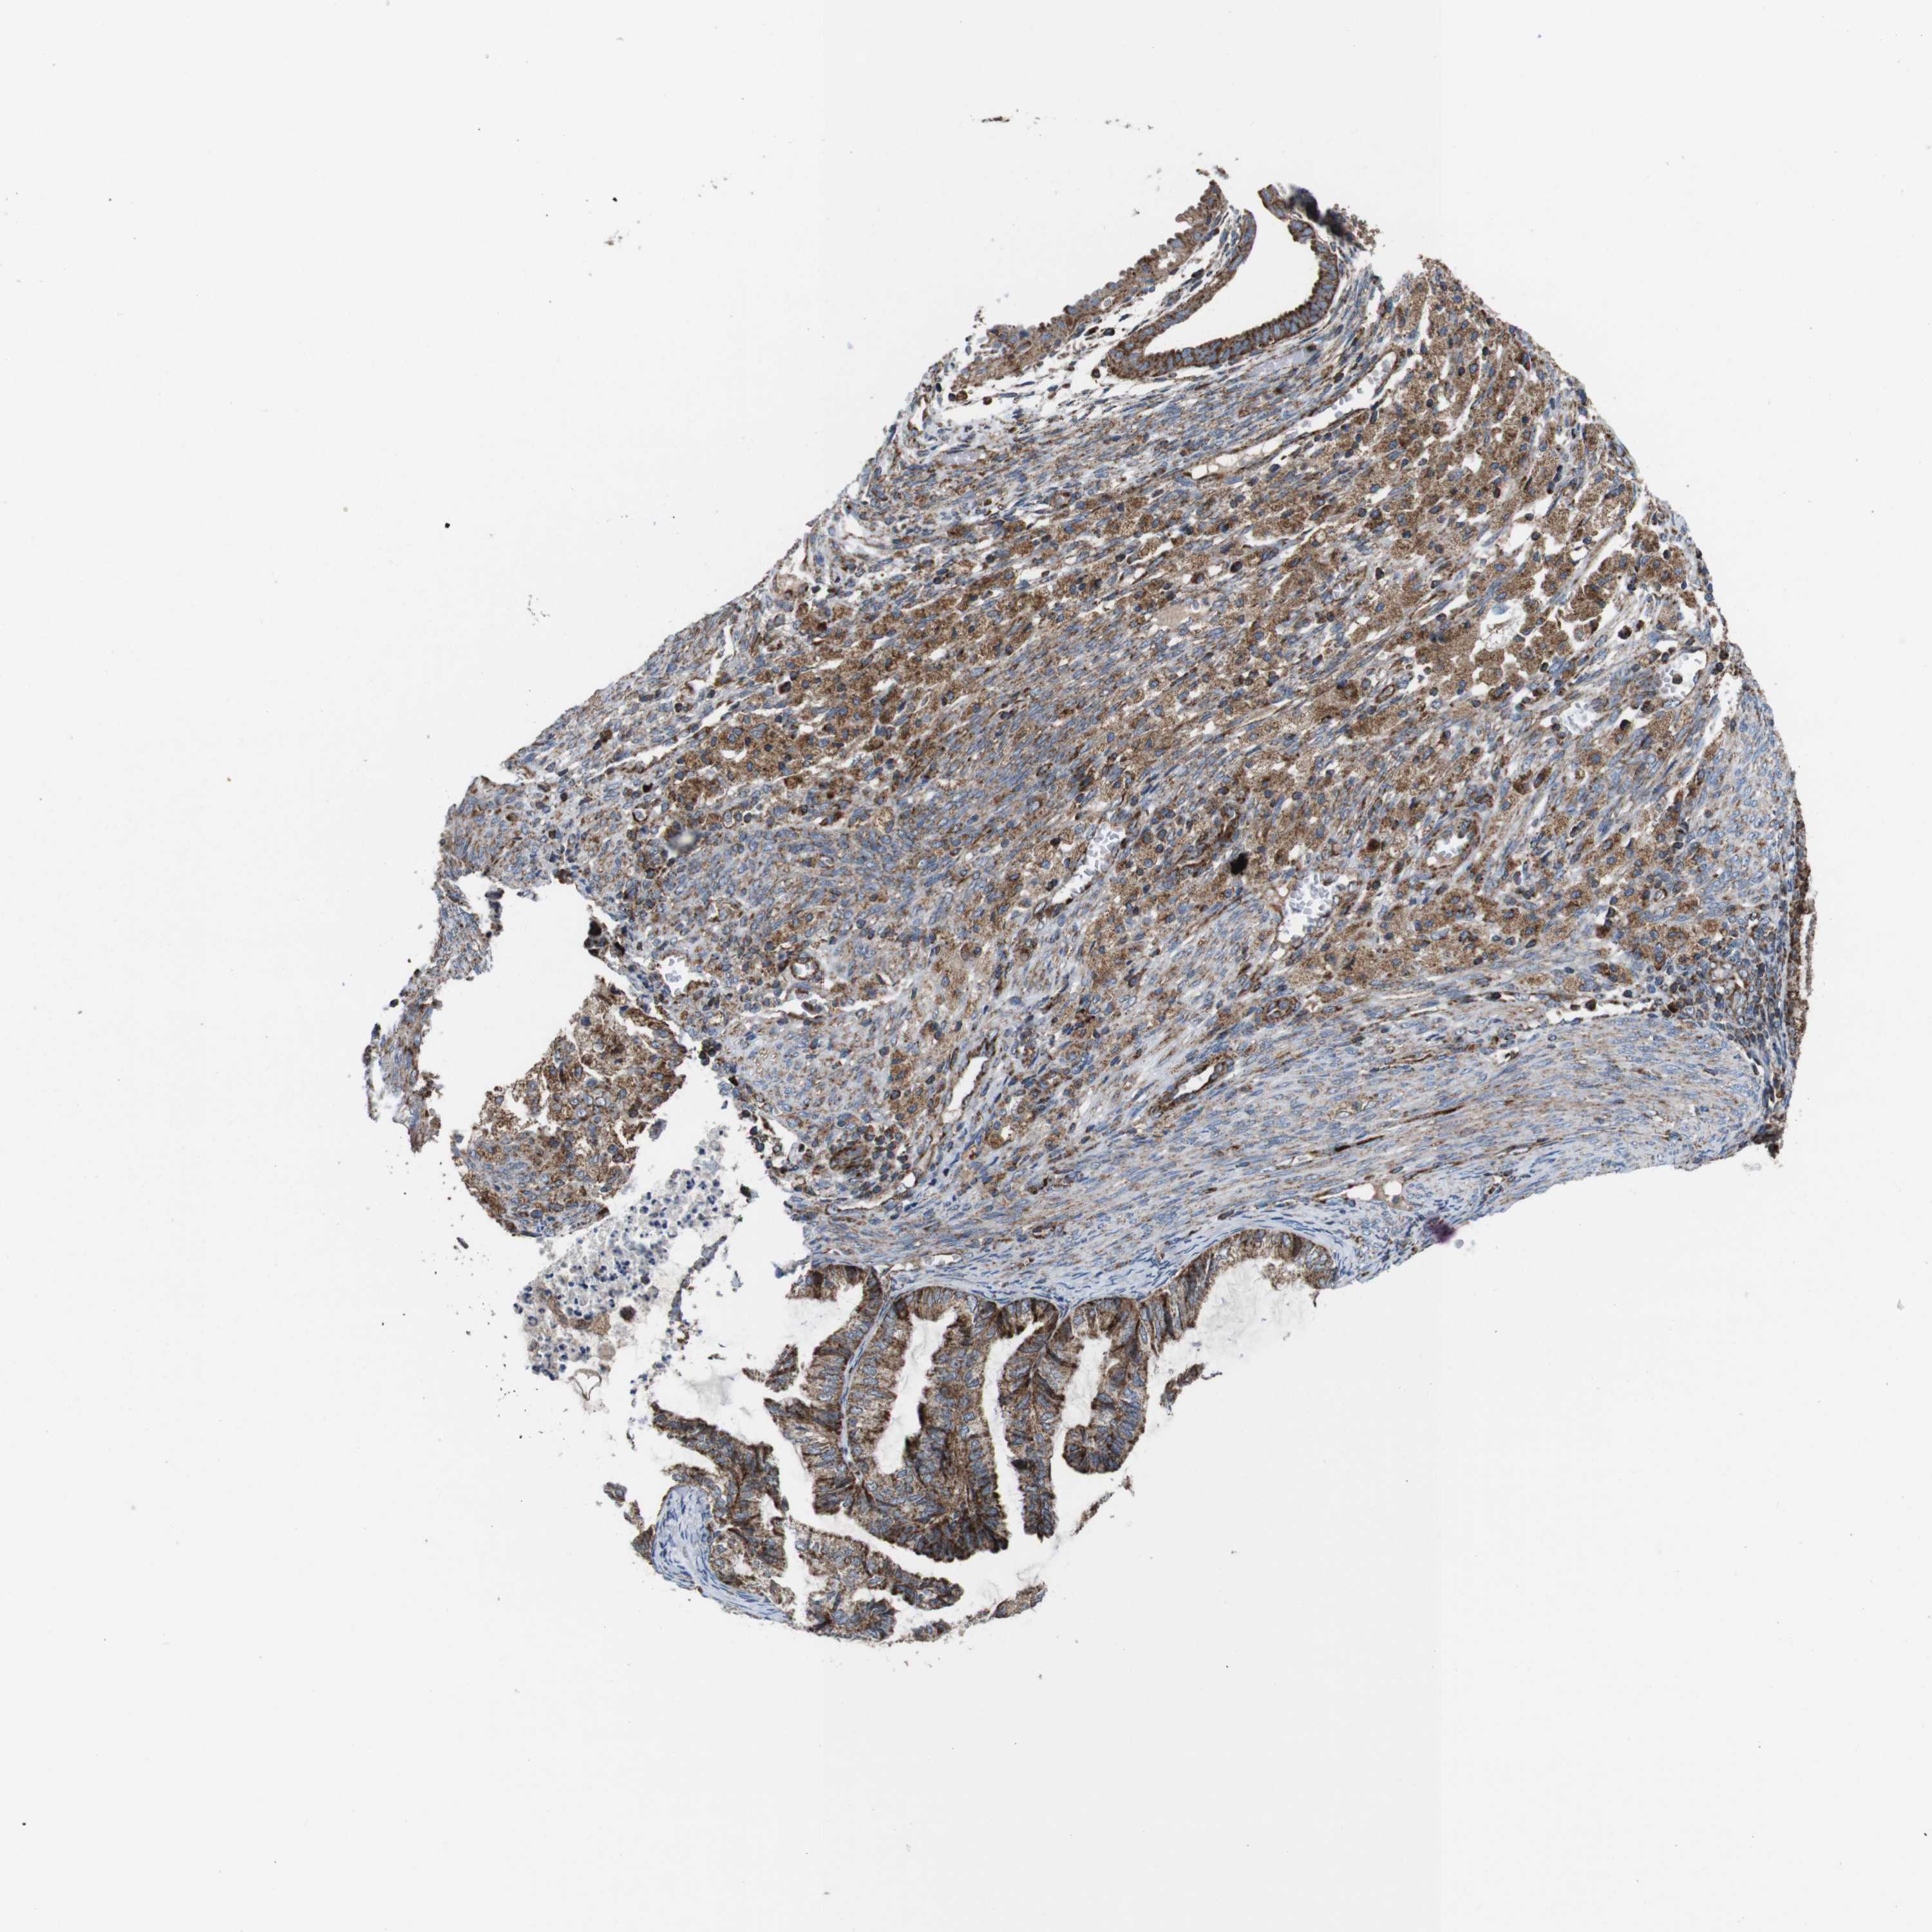

CERVICAL CANCER - Protein expressioni

A mouse-over function shows sample information and annotation data. Click on an image to view it in a full screen mode. Samples can be filtered based on level of antibody staining by selecting one or several of the following categories: high, medium, low and not detected. The assay and annotation is described here.

Note that samples used for immunohistochemistry by the Human Protein Atlas do not correspond to samples in the TCGA dataset.

Antibody stainingi

Antibody staining in the annotated cell types in the current human tissue is reported as not detected, low, medium, or high, based on conventional immunohistochemistry profiling in selected tissues. This score is based on the combination of the staining intensity and fraction of stained cells.

Each image is clickable and will lead to virtual microscopy that enables deeper exploration of all samples and also displays staining intensity scores, fraction scores and subcellular localization as well as patient and tissue information for each sample.

Antibody HPA007043

Antibody HPA007044

Antibody CAB010052

Squamous cell carcinoma, NOS

Adenocarcinoma, NOS